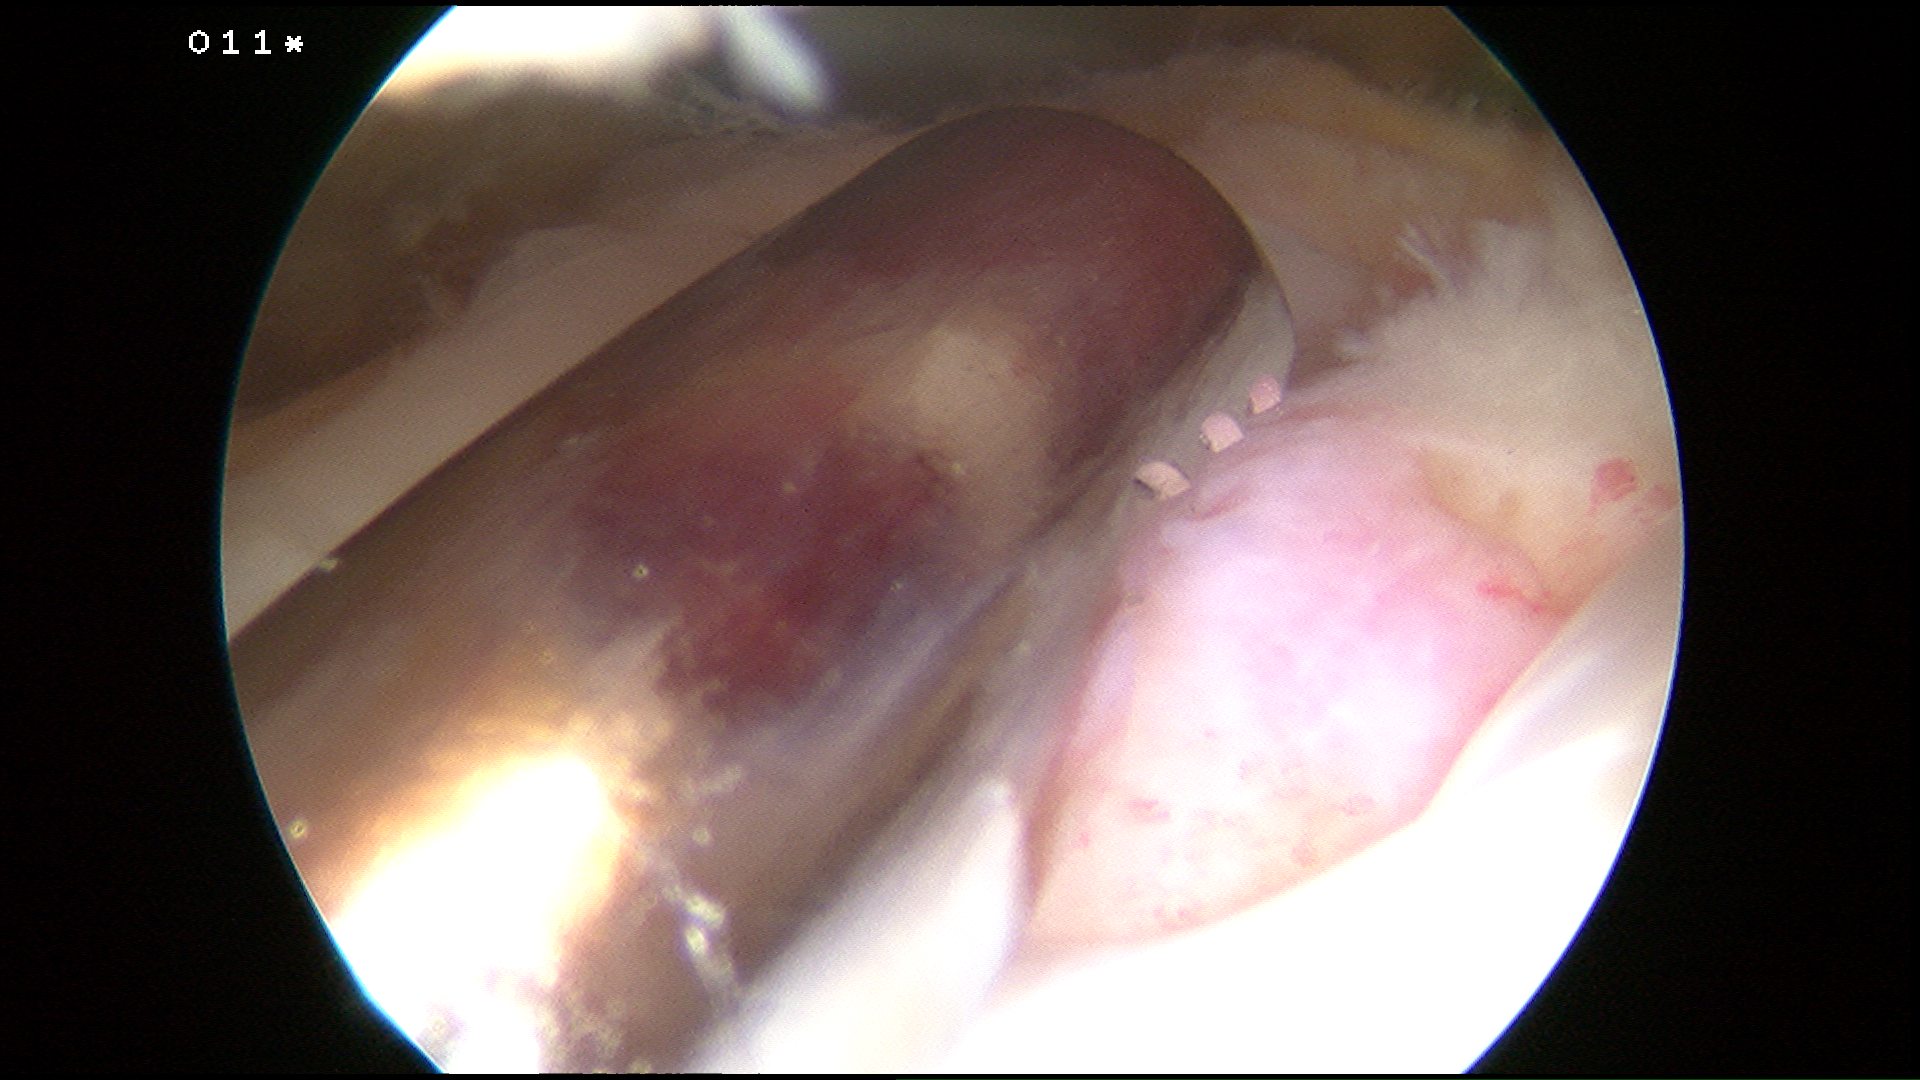

1. Footprint

- 25 x 15 mm

- healing zone

- the greater the extent a repair covers, the greater the chance for tendon bone healing

Prepare insertion

- debride tendon edges

- debride footprint to punctate bleeding